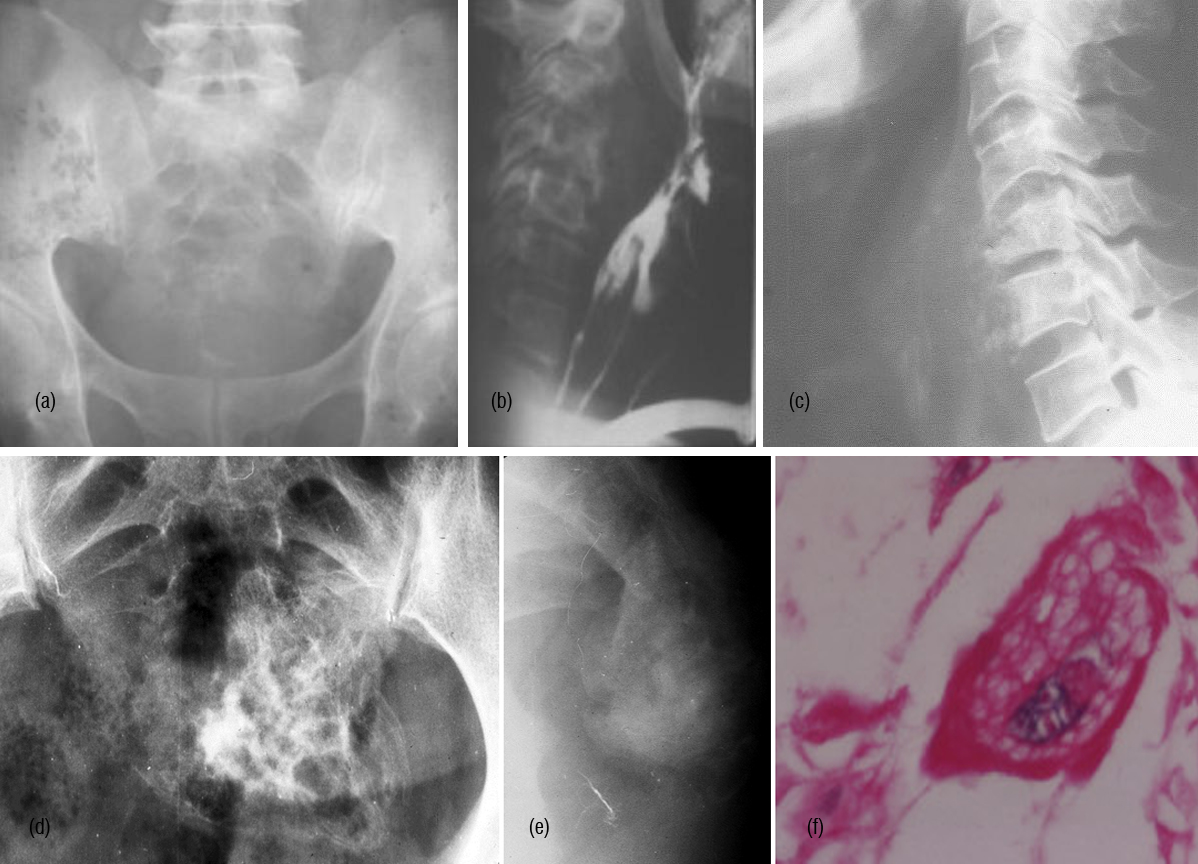

It radiologically shows a spectrum of manifestations. The bones particularly, in axial skeleton may present with multiple compression fractures. In 10-15% of cases, classical punched out lesions of the skull may be noted. In long tubular bones, pathological fractures are common with associated soft tissue swelling. In early skeletal lesions, moth eaten type of appearance is observed without any periosteal reaction (Figure 6ab). MRI is more sensitive to depict bone marrow lesions, whereas radionuclide scintigraphy with technetium 99 compounds is not that sensitive (Figure 7abcdef). The radiological appearances are listed in Table 3.

Figure 6: Multiple Myeloma – (a) Diffuse osteopenia with loss of trabeculae, (b) lytic lesions in the bodies.

Figure 7: (a,b,c) Multiple myeloma with osteopenia and early collapse of vertebral bodies BC MRI of the same patient. (d) plain films, (e, f) MRI.